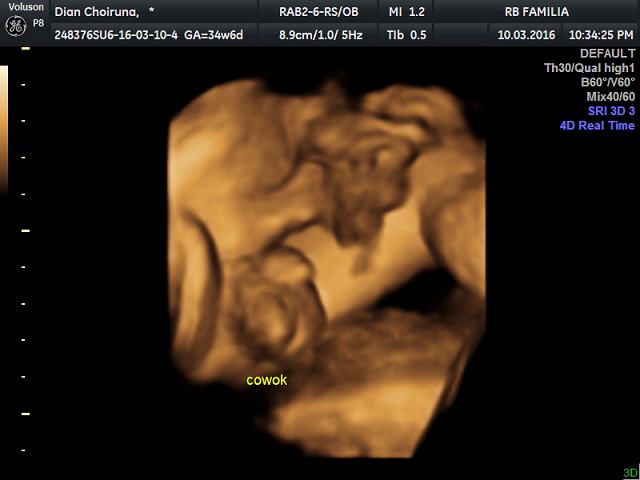

Gambar Hasil Usg Janin Perempuan : Perbedaan Jenis Kelamin Laki Laki Dan Perempuan - Tips .... Manfaat usg 3 dimensi sama seperti usg 2 dimensi, usg 3 dimensi menggunakan gelombang suara berfrekuensi tinggi dan peranti lunak (software) khusus untuk menangkap gambar. Bahkan pada janin yang lebih besar bisa tampak buah zakar yang berada dalam kantung zakar. Saat hamil, penting untuk melakukan pemeriksaan ultrasonografi (usg). Usg jenis kelamin janin usia 5 bulan dengan 4d maupun 2d sudah kelihatan. Ini adalah istilah yang diberikan untuk labia dan klitoris pada janin perempuan.

Hasil usg 4d bayi umur 8 bulan ( jenis kelamin perempuan ). Moms, begini caranya membaca hasil usg : Nah, tapi ada juga nih yang masih bingung. Gambar bayi yang bisa anda lihat juga tergantung dari sudut tembakan dari transduser usg atau alat yang dipakai untuk mengambil gambar usg. Biasanya parents akan ditunjukkan gambar hasil pemindaian rahim pada layar oleh dokter dan diberikan foto hasil cetaknya. Cara membaca gambar hasil usg bayi untuk jenis kelamin ada sejumlah faktor penentu yang membantu calon orang tua mengetahui jenis kelamin janin melalui gambar usg. Contohnya seperti yang dilakukan wanita asal swedia yang merupakan calon ibu dari 2 bayi kembar ini. Oleh karenanya, tingkat kesalahan identifikasi janin perempuan lebih besar daripada janin laki2. Bahkan pada janin yang lebih besar bisa tampak buah zakar yang berada dalam kantung zakar. Melalui hasil usg, dokter dan ibu hamil dapat mengetahui kondisi janin dalam kandungan. Usg umur 6 bulan,usg umur 7 bulan, hasil usg janin umur 8 bulan Janin yang terlihat tersebut masih berupa titik janin saat usia kehamilan masih 5 minggu. Walaupun ukurannya masih kecil sekali tetapi janin sudah bisa terlihat dalam pemeriksaan usg.

Hasil usg 4d bayi umur 8 bulan ( jenis kelamin perempuan ).